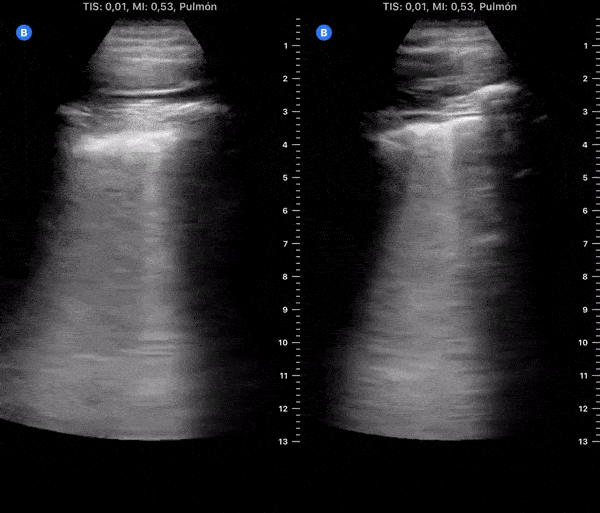

COVID 19 Lung US Disease Progression - Day 10

Day 10 after #COVID diagnosis. Less tired, but more cough, ageusia & anosmia. No dyspnea or red flag symptoms. No fever. SpO2 97%. #POCUS update: Right, Left lower & lateral with thick pleural line & focal B-lines. @yaletung